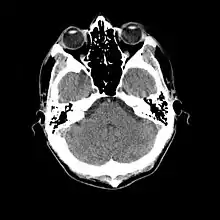

- Cranial computed tomography (CT, invented 1972) proved to be an excellent tool for diagnosing cerebral neoplasms in children, including those found in tuberous sclerosis.[46]

- MR was judged superior to CT imaging for both sensitivity and specificity. In a study of fifteen patients, it identified subependymal nodules projecting into the lateral ventricles in twelve patients, distortion of the normal cortical architecture in ten patients (corresponding to cortical tubers), dilated ventricles in five patients, and distinguished a known astrocytoma from benign subependymal nodules in one patient.[53]

- MR imaging was found to be capable of predicting the clinical severity of the disease (epilepsy and developmental delay). A study of 25 patients found a correlation with the number of cortical tubers identified. In contrast, CT was not a useful predictor, but was superior at identifying calcified lesions.[54]

- Cortical tubers found on MR imaging corresponded exactly to the location of persistent EEG foci, in a study of six children with TSC. In particular, frontal cortical tubers were associated with more intractable seizures.[56]

- MRI with fluid attenuated inversion recovery (FLAIR) sequences was reported to be significantly better than standard T2-weighted images at highlighting small tubers, especially subcortical ones.[62][63]